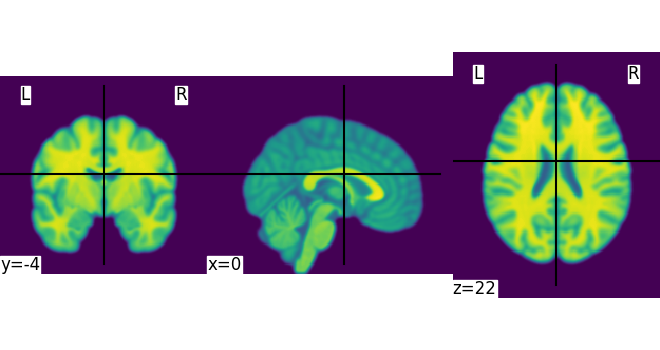

Simple image manipulation: smoothing¶

Let’s use an image-smoothing function from nilearn:

nilearn.image.smooth_img

Functions containing ‘img’ can take either a filename or an image as input.

Here we give as inputs the image filename and the smoothing value in mm

from nilearn import image

smooth_anat_img = image.smooth_img(MNI152_FILE_PATH, fwhm=3)

This is an in-memory object. We can pass it to nilearn function, for instance to look at it

<nilearn.plotting.displays._slicers.OrthoSlicer object at 0x7f3bb4eb0d10>